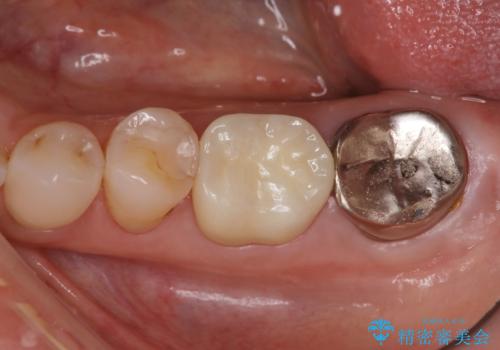

- 他院で、仮歯にしたがセラミックの値段が高すぎると思ったため治療相談も含めて来院された患者様です。

仮歯を新調させていただき、再度虫歯治療を行なって、歯の形を作りセラミックを入れさせていただきました。

フルジルコニアクラウン 7万円(税抜)

仮歯 1万円

にて治療させていただきました。色に関しても喜んでいただき満足されていました。